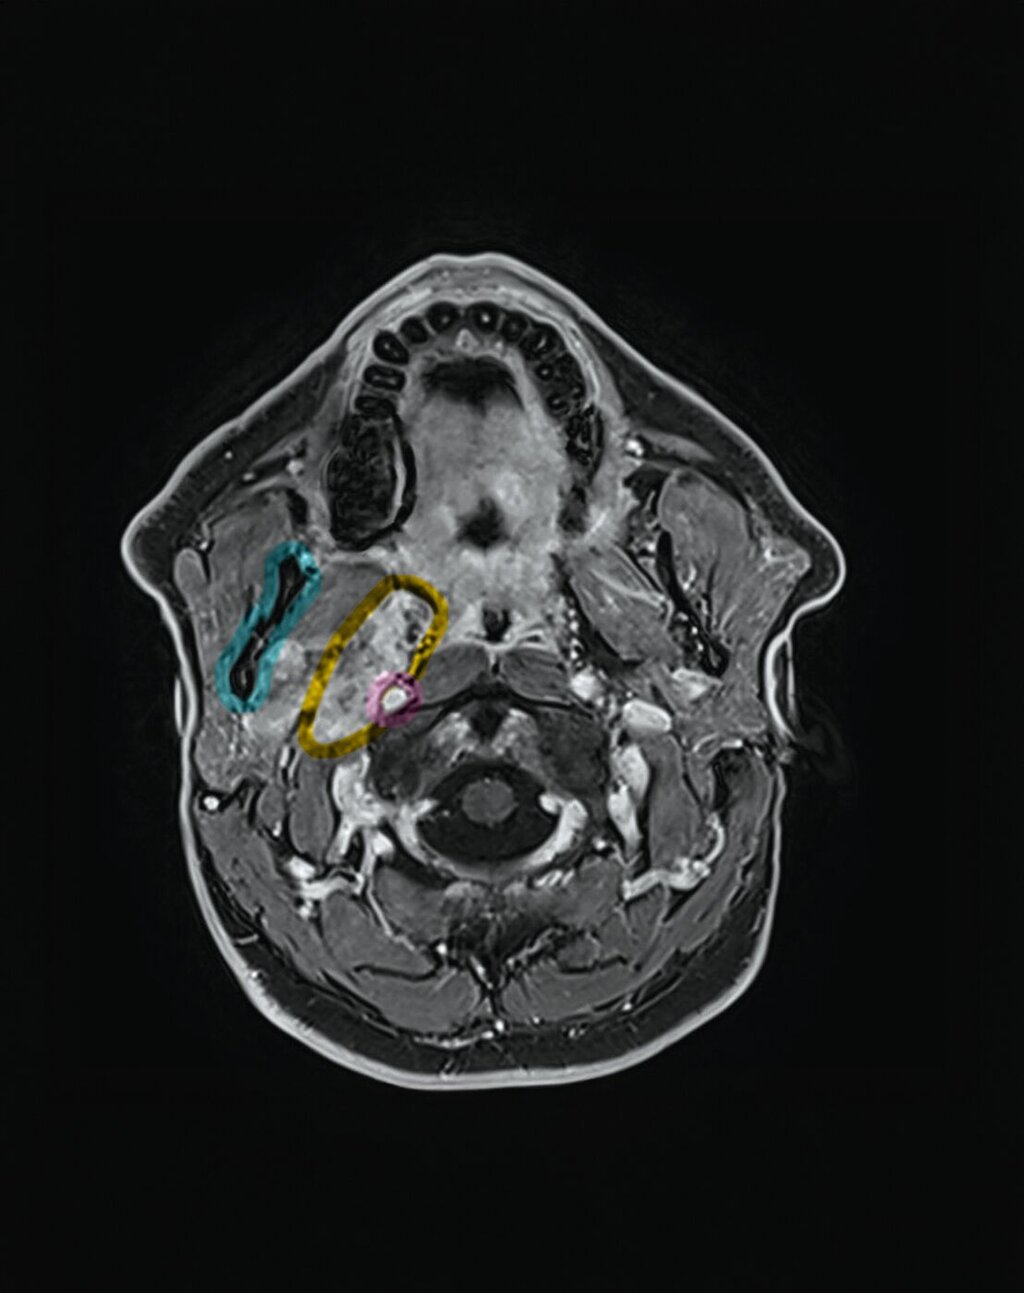

Ein vaskulärer Ursprung konnte mittels dynamischer Sequenzen ausgeschlossen werden. Die Raumforderung wuchs verdrängend bis an den Musculus pterygoideus heran und hatte einen langstreckigen Kontakt von > 90° zur A. carotis interna. Zusätzlich bestand eine schlitzförmige Kompression der V. jugularis interna sowie eine fokale Teilthrombosierung der V. facialis communis. Pathologisch vergrößerte Lymphknoten waren nicht nachweisbar.

Zur besseren räumlichen Einschätzung wurde das MRT-Datenset mittels der Open-Source-Software 3D Slicer segmentiert [Fedorov et al., 2012]. Mithilfe der Funktion „Grow from seeds“ erfolgte eine separate Segmentierung des Unterkiefers und der Raumforderung, ergänzt durch manuelle Korrekturen.

Metallartefakte durch zahnärztliche Restaurationen im rechten Unterkiefer wurden berücksichtigt. Die dreidimensionale Rekonstruktion verdeutlichte die enge Beziehung des Tumors zur A. carotis interna und unterstützte die Indikationsstellung für einen erweiterten operativen Zugang.

Nach Darstellung der Gefäß‑Nerven‑Straße wurden die A. carotis communis sowie die A. carotis interna freipräpariert. Die A. carotis interna wurde vorsorglich mit einem Gefäßloop unterfahren und gesichert. Anschließend erfolgten die Mobilisation der Glandula parotis sowie die Darstellung des Kieferwinkels.